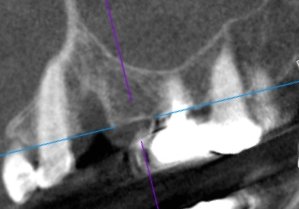

CT撮影の必要性について

インプラント症例その8

インプラント症例その7